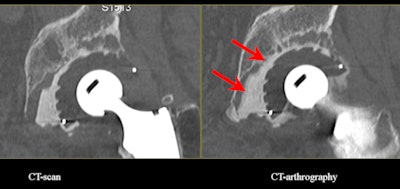

![]() |

| Acetabular loosening. CT arthrography clearly shows the diffusion of contrast medium around the cement in zones II and III. (Provided by Prof. Alain Blum) |

"There are some previous studies that show arthrography with subtraction is a good technique to detect some loosening and especially acetabular loosening," he stated. "If you combine arthrography with CT, you enhance the formation of those techniques."